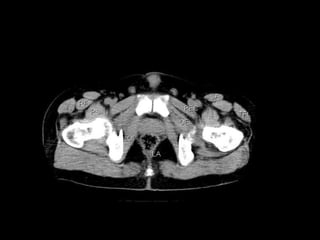

Radiographers use medical imaging equipment like X-rays and MRIs to produce images of patients' internal structures and organs. They are responsible for positioning patients, operating scanning machines, and ensuring quality images. Radiographers must have strong attention to detail, excellent communication skills, and the ability to work well under pressure to accurately capture anatomical features and diagnose any abnormalities.